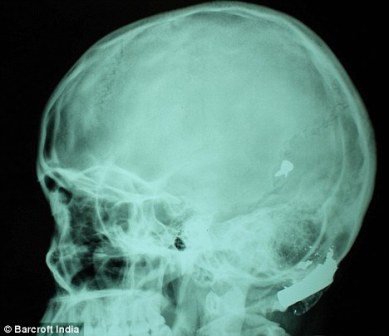

其中一顆子彈擊中她的左中耳,穿透了她的耳骨,然后擊中頭骨,嵌在了腦子里。另外兩顆子彈分別擊中她的右臂和心臟。印度Lok Nayak醫(yī)院的醫(yī)生稱,赫娜能夠康復完全是奇跡,她也足夠幸運。她的主治醫(yī)生稱:“當我們看到她的情況時,被嚇了一跳,幸運的是她活了下來!

這顆子彈沒有損壞大腦中控制身體機能的部分。盡管赫娜的手術(shù)很成功,但醫(yī)生表示,她還有出現(xiàn)感染和并發(fā)癥的可能。子彈毀掉了她的中耳,可能導致她耳聾。(楊柳)